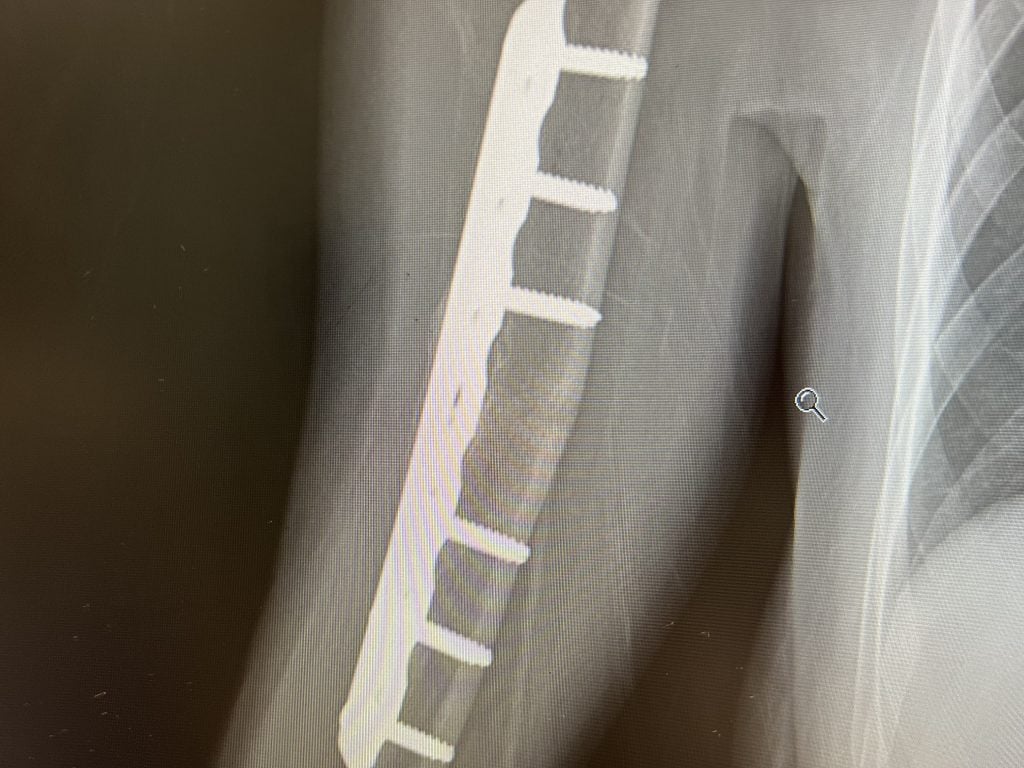

I broke my arm on August 11, 2022 after having a traumatic fall off my horse. I live in Charlotte, NC. After trying to heal naturally for 3 months I was frustrated with my doctor as he couldn’t tell me why I wasn’t able to heal. I then found out about HSS and found Dr. Sama. I had a virtual appointment with him in November 2022. He spent almost an hour on the virtual call with me and my husband. After that appointment I knew that I would have no one but Dr. Sama operate on me. On January 5th he performed an open reduction internal fixation on the transverse fracture of my humerus in my dominant right arm. Today, May 3rd, almost 4 months later I had my final follow up with him. He said that my fracture is officially healed! I’ve been working hard every single day to get both mobility and strength back in my arm. I’m back doing all the activities I love! I cannot thank Dr. Sama enough for everything. He is the BEST!